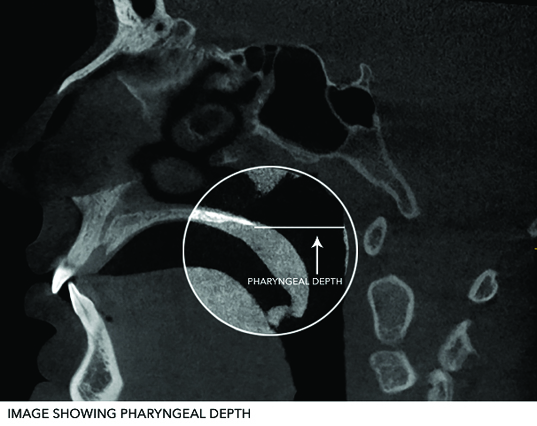

According to our knowledge there have been no studies done to determine varied soft palate morphology and configuration using CBCT. So, the purpose of this present study was to investigate the variation in morphology of soft palate in different age and gender groups, and to find its association with the Need’s ratio, radiographic Velar Length (VL), Velar Width (VW) and Pharyngeal Depth (PD) in different morphological velar types, age groups and gender using CBCT in Central Madhya Pradesh population.

During resting position of soft palate,

PD = Linear distance from posterior surface of nasal spine to posterior pharyngeal wall along palatal plane [1] [Table/Fig-7,8 and 9].

Image showing pharyngeal depth.

The measurements were carried out for each digital scan using Kodak software, twice by the same examiner, and the obtained mean value was considered. The Need’s ratio was calculated for all the subjects by the division of PD by VL.

The mean velar length and pharyngeal depth were the smallest in butt shape and handle shape while maximum in leaf shape and crook shape soft palates, respectively [Table/Fig-12]. The mean velar width was the shortest in S-shape and maximum in leaf shape, whereas the Need’s ratio was found to be the lowest and equal in both, leaf and S-shape and the highest in crook shape velar morphology. The Need’s ratio ranged from 0.29 to 1.22, had 95.0% confidence interval ranging from 0.68 to 0.74.

The statistical agreement based on one-way analysis of variance (ANOVA) highlighted that the mean differences in morphological variants: velar length velar width, pharyngeal depth and Need’s ratio were not significant (p>0.05) among morphological types of the soft palate. So it was concluded that types of soft palate cannot be identified by calculating velar length, velar width, pharyngeal depth and Need’s ratio.

The statistical agreement based on one-way analysis of variance (ANOVA) reported that the mean differences in morphological variants: velar length (p<0.005) and pharyngeal depth (p<0.001) were highly significant but velar width (p>0.05) and Need’s ratio (p>0.05) weren’t significant among different age groups [Table/Fig-14]. This concluded that velar length and pharyngeal depth increases with age while Need’s ratio and velar width had no significance.